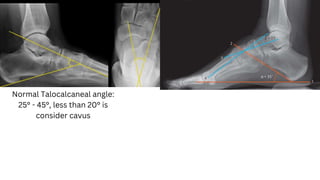

Normal calcaneal pitch 17°-

32°

Meary angle Normal range : 0° more than 4° is consider cavus

Normal Talocalcaneal angle:

25° - 45°, less than 20° is

consider cavus